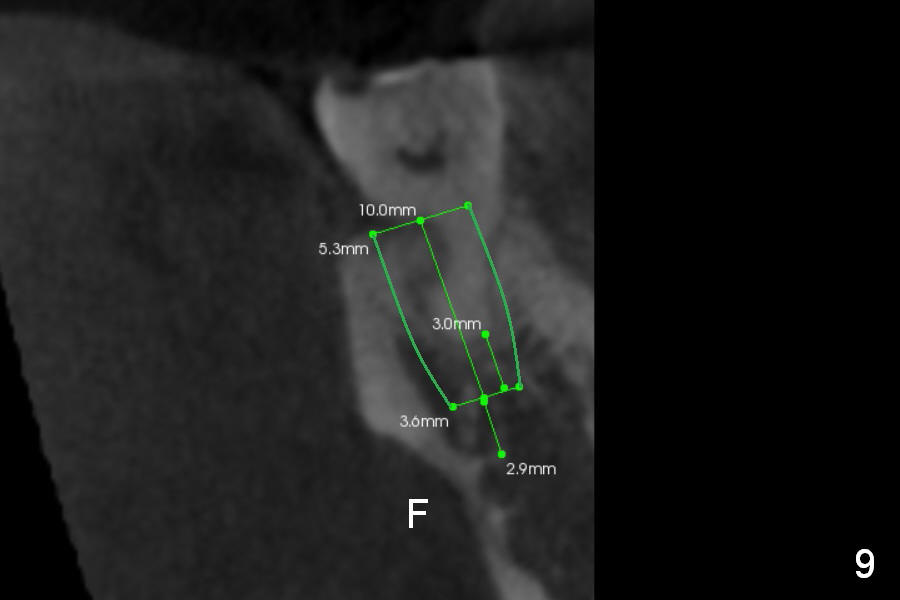

CBCT Analysis of the lower left 2nd molar reveals that the proper implant size is 5.3x10 mm (Fig.8-10). The root is C shaped; limiting factor is buccolingual width (5.5 mm, Fig.8 (axial section)). The major difference between #18 and 31 is the resorption of the buccal plate of the latter (traumatic extraction, Fig.9 (F: submandibular fossa)).